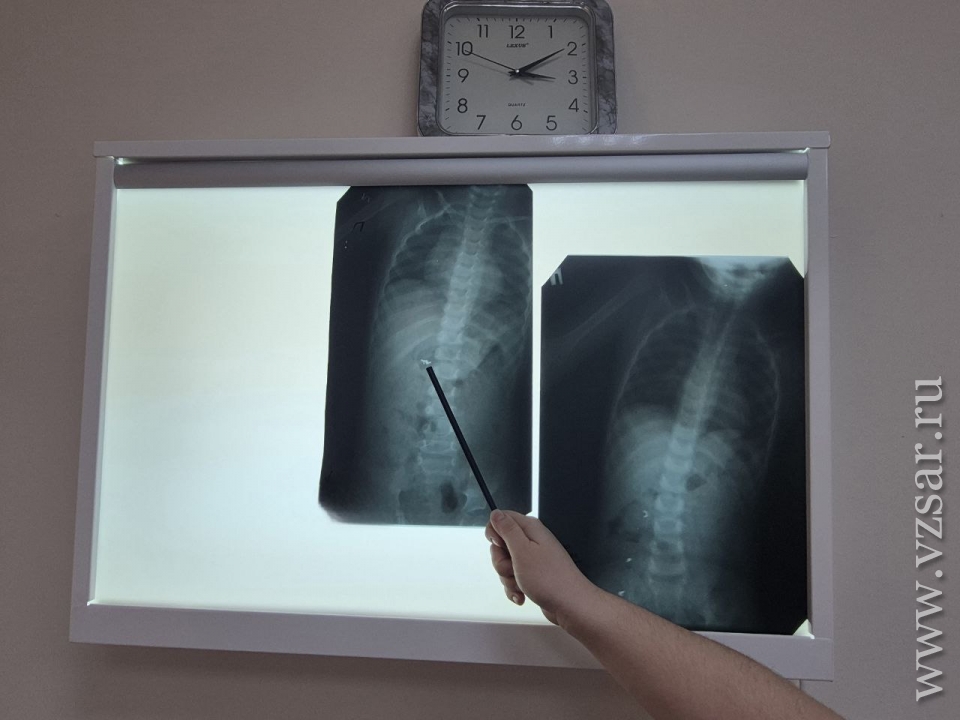

"Семья отправилась в Хвалынскую больницу, где ребенку был выполнен рентгеновский снимок, который показал наличие инородного тела в желудке. Юного пациента перенаправили в БГКБ. Контрольный снимок отчетливо показал, что, во-первых, инородное тело состоит из трех частей, а во-вторых, что они находятся уже не в желудке, а распределились по кишечнику", - рассказали врачи.